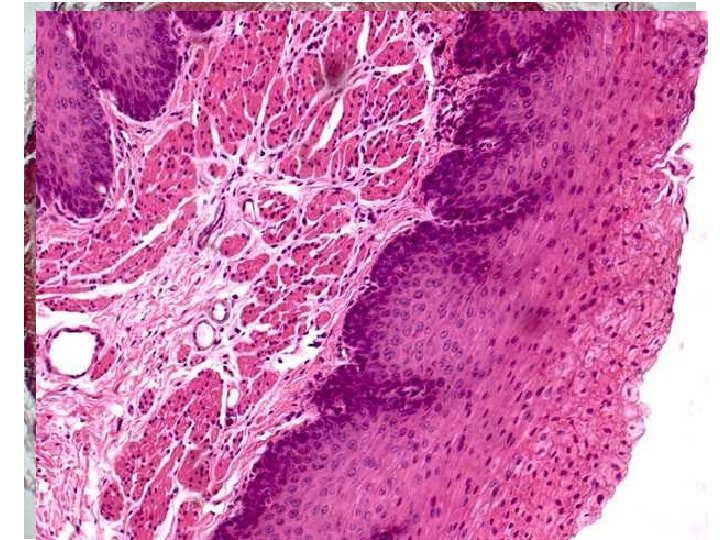

Transition: Pylorus - Duodenum HE

Duodenum - HE